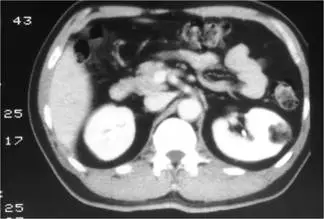

45歲女性病人接受年度健康檢查,發現左腎腫瘤,下圖為注射對比劑之腎臟電腦斷層攝影( computed tomography of kidneys ),最可能之診斷為何?

對於腎臟腫瘤,電腦斷層(CT)上「腫瘤內度量值為負值(negative attenuation)之脂肪成分」幾乎是診斷angiomyolipoma(AML)的關鍵。本題重點在於如何利用CT影像上的組織密度差異,分辨含脂性良性腫瘤與其他惡性腎腫瘤。

在題示對比劑增強CT冠狀切面影像中,左腎下極可見一圓形、邊界清楚之腫塊,於腫塊內有數處非常低密度區(呈黑色),這些區域在Hounsfield單位上應小於–10 HU,符合macroscopic fat的影像特徵;增強期可見周邊及基質成分輕度增強,未見廣泛壞死或鈣化。這種「腫瘤內可直接看到脂肪」的影像表現,與典型的angiomyolipoma極為吻合 (radiologica.org)。